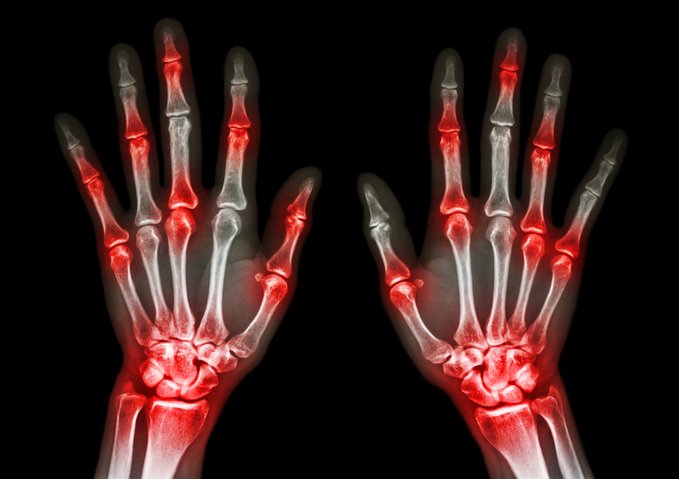

Uso de alopurinol y riesgo de síndrome coronario agudo en pacientes con gota:  estudio de cohorte poblacional

En pacientes con gota y sin enfermedad coronaria, el uso prolongado de alopurinol protege contra el primer síndrome coronario agudo (SCA) en comparación con los no usuarios. Por el contrario, los iniciadores del alopurinol, que posiblemente tenían más inflamación sistémica, tenían un mayor riesgo de SCA por primera vez en comparación con los usuarios a largo plazo. BMJ Open, 27 de febrero de 2025